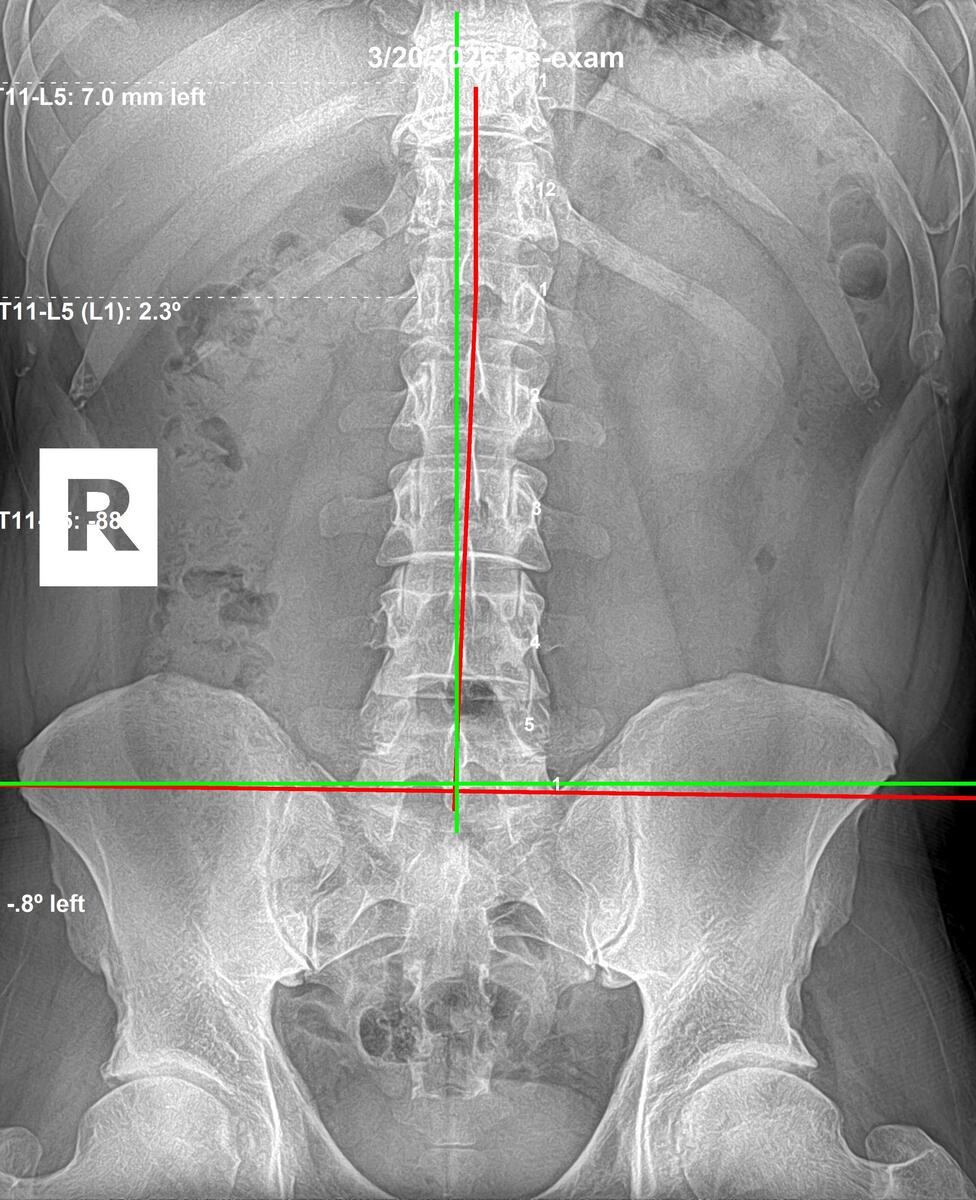

Follow-up lumbar AP X-ray showing left AI sacrum corrected from 2.3 degrees to 0.8 degrees after 12 weeks, March 20 2026, Rochet Family Chiropractic Royal Palm Beach

After 12 Weeks — March 20, 2026

Lumbar (AP): Left AI sacrum corrected from 2.3° to 0.8°. Sacral base leveling, lumbar foundation stabilizing.